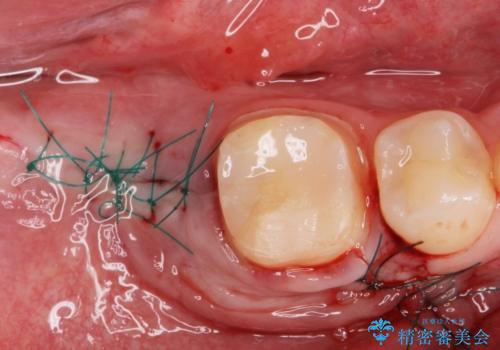

抜歯したところは抜歯後骨の治癒を待ち、CTを撮影しインプラント治療ができる事(骨の厚みなど)確認し治療を行いました。

白くて綺麗な被せ物が入りました。

インプラントを入れた後は定期的なメンテナンスが必要になります。